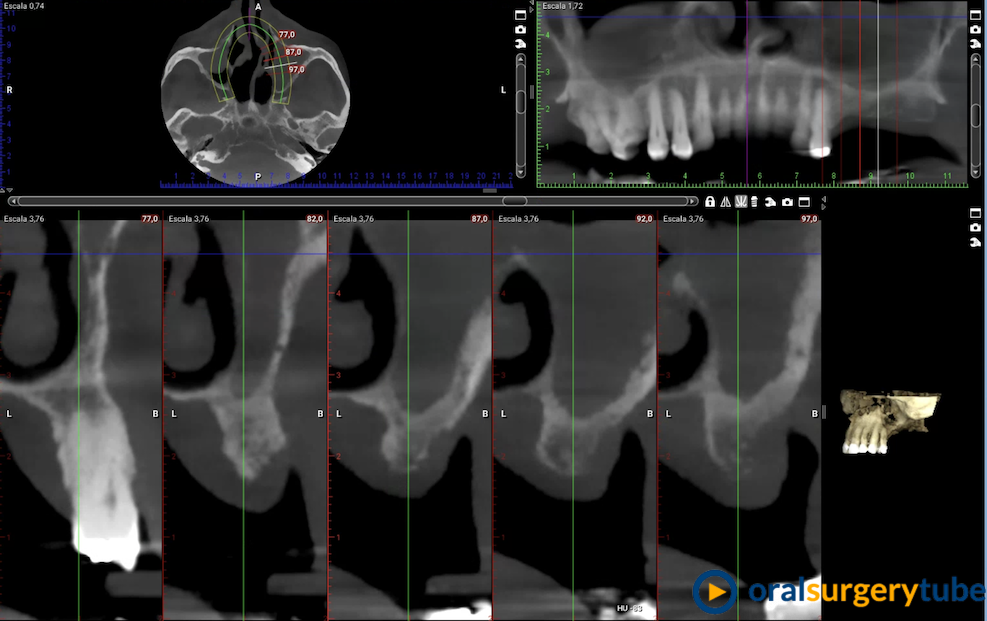

REGENERACIÓN OSEA DEL CUADRANTE 2

Buenos dias, queria regenerar con altura y anchura el cuadrante dos.